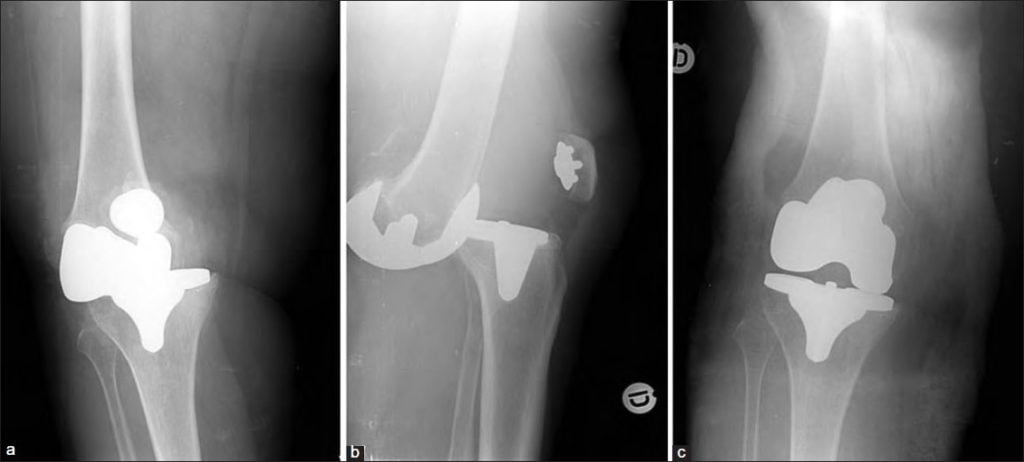

Повторный вывих или перелом

Имплантат устанавливается на место поврежденного сустава с точностью до миллиметра. При помощи компьютерной визуализации проводится проверка кинематики в согнутом/разогнутом положении. 1-1,2% случаев заканчивается повторным вывихом или переломом эндопротеза. В редких ситуациях проблема вызвана неправильной установкой или некачественным протезом, 98% пациентов создают себе проблему, игнорируя рекомендации по реабилитации.

Главный признак перелома – хруст внутри коленного сустава. Если на раннем этапе такой симптом можно объяснить врачебной ошибкой или постоперационным осложнением, то в дальнейшем хруст свидетельствует о нарастании рубцовой ткани. Неправильное восстановление идет из-за несоблюдения режима и диеты.

При появлении хруста не ждите дальнейших осложнений. Обратитесь к специалисту для коррекции дефектов. Часто можно обойтись терапевтическим воздействием, избежать ревизии.